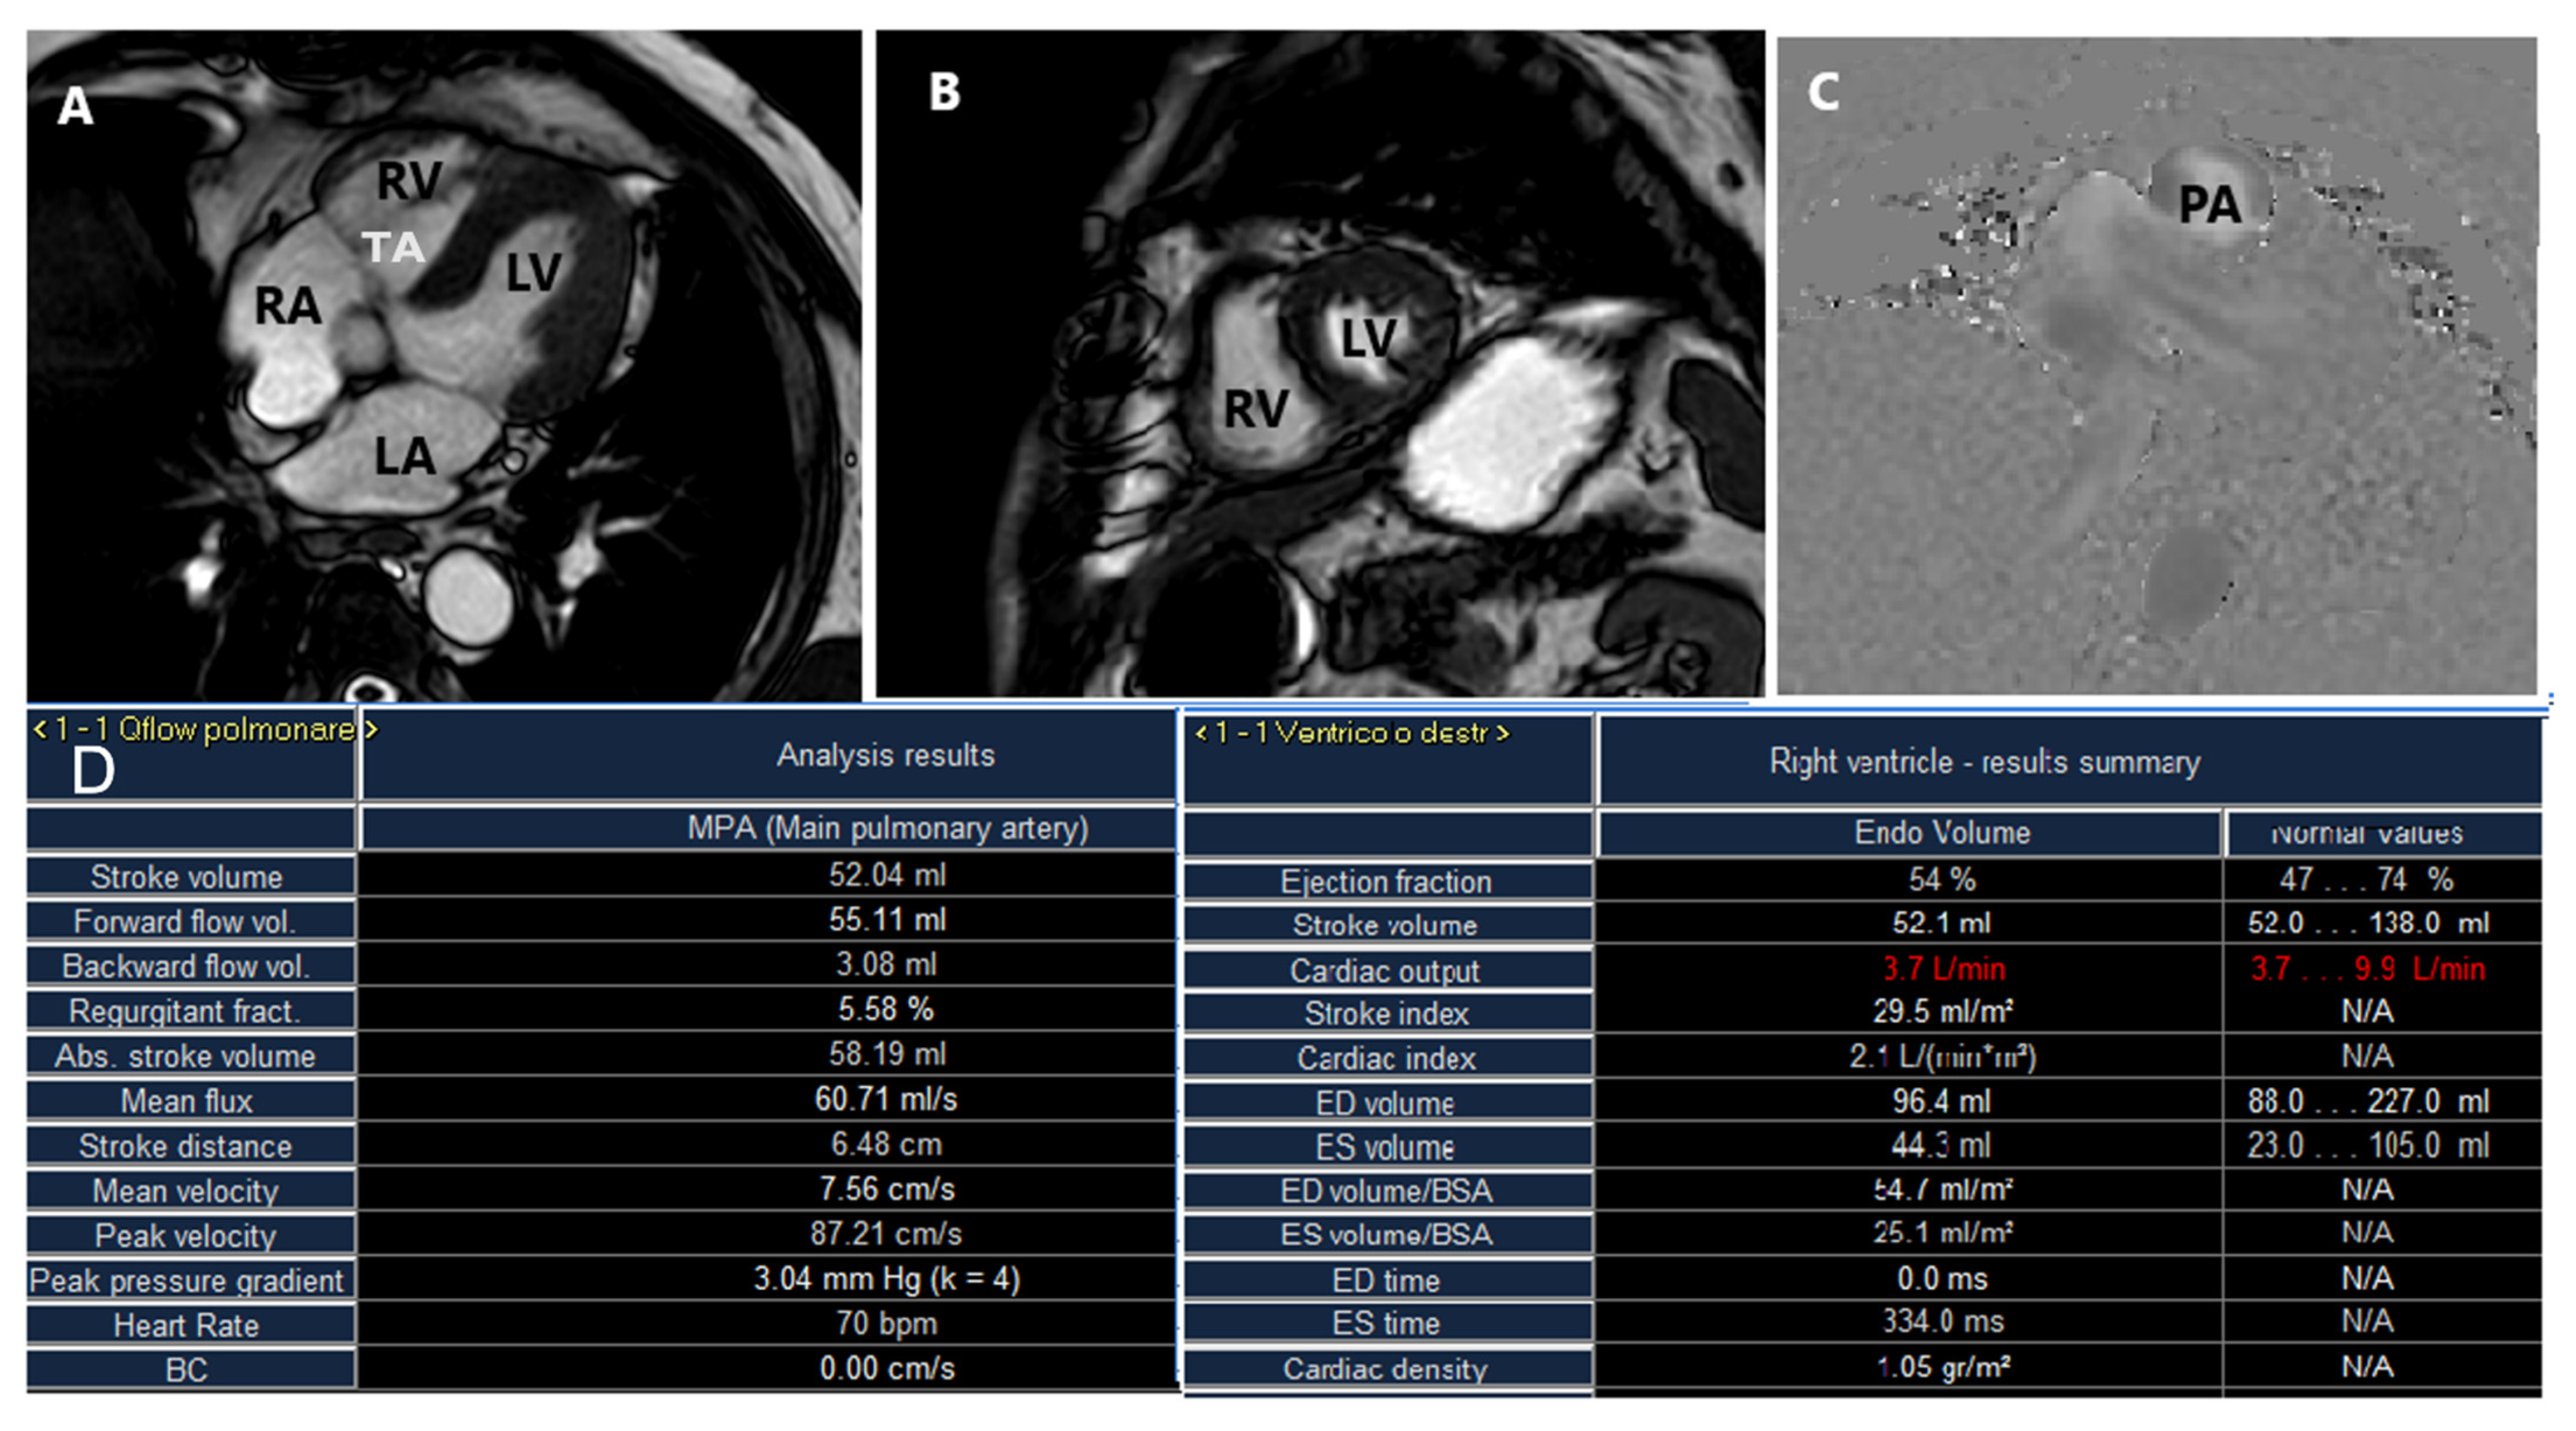

2.3. Cardiac Magnetic Resonance

- Hashimoto, G.; Fukui, M.; Sorajja, P.; Cavalcante, J.L. Essential roles for CT and MRI in timing of therapy in tricuspid regurgitation. Prog. Cardiovasc. Dis. 2019, 62, 459–462. [Google Scholar] [CrossRef] [PubMed]

- Cavalcante, J.L.; Lalude, O.O.; Schoenhagen, P.; Lerakis, S. Cardiovascular Magnetic Resonance Imaging for Structural and Valvular Heart Disease Interventions. JACC Cardiovasc. Interv. 2016, 9, 399–425. [Google Scholar] [CrossRef] [PubMed]

- Hundley, W.G.; Bluemke, D.A.; Finn, J.P.; Flamm, S.D.; Fogel, M.A.; Friedrich, M.G.; Ho, V.B.; Jerosch-Herold, M.; Kramer, C.M.; Manning, W.J.; et al. ACCF/ACR/AHA/NASCI/SCMR 2010 Expert Consensus Document on Cardiovascular Magnetic Resonance: A Report of the American College of Cardiology Foundation Task Force on Expert Consensus Documents. J. Am. Coll. Cardiol. 2010, 55, 2614–2662. [Google Scholar] [CrossRef] [PubMed]

- Zhan, Y.; Debs, D.; Khan, M.A.; Nguyen, D.T.; Graviss, E.A.; Khalaf, S.; Little, S.H.; Reardon, M.J.; Nagueh, S.; Quiñones, M.A.; et al. Natural History of Functional Tricuspid Regurgitation Quantified by Cardiovascular Magnetic Resonance. J. Am. Coll. Cardiol. 2020, 76, 1291–1301. [Google Scholar] [CrossRef] [PubMed]

- Park, J.-B.; Kim, H.-K.; Jung, J.-H.; Klem, I.; Yoon, Y.E.; Lee, S.-P.; Park, E.-A.; Hwang, H.-Y.; Lee, W.; Kim, K.-H.; et al. Prognostic value of cardiac MR imaging for preoperative assessment of patients with severe functional tricuspid regurgitation. Radiology 2016, 280, 723–734. [Google Scholar] [CrossRef] [PubMed]

- Kresoja, K.-P.; Rommel, K.-P.; Lücke, C.; Unterhuber, M.; Besler, C.; von Roeder, M.; Schöber, A.R.; Noack, T.; Gutberlet, M.; Thiele, H.; et al. Right Ventricular Contraction Patterns in Patients Undergoing Transcatheter Tricuspid Valve Repair for Severe Tricuspid Regurgitation. JACC Cardiovasc. Interv. 2021, 14, 1551–1561. [Google Scholar] [CrossRef]

- García-Alvarez, A.; Friera, L.F.; Mirelis, J.G.; Sawit, S.; Nair, A.; Kallman, J.; Fuster, V.; Sanz, J. Non-invasive estimation of pulmonary vascular resistance with cardiac magnetic resonance. Eur. Heart J. 2011, 32, 2438–2445. [Google Scholar] [CrossRef]

- Rommel, K.-P.; Besler, C.; Noack, T.; Blazek, S.; von Roeder, M.; Fengler, K.; Ender, J.; Gutberlet, M.; Desch, S.; Borger, M.A.; et al. Physiological and Clinical Consequences of Right Ventricular Volume Overload Reduction after Transcatheter Treatment for Tricuspid Regurgitation. JACC Cardiovasc. Interv. 2019, 12, 1423–1434. [Google Scholar] [CrossRef] [PubMed]

- Kim, H.-K.; Kim, Y.-J.; Park, E.-A.; Bae, J.-S.; Lee, W.; Kim, K.-H.; Kim, K.-B.; Sohn, D.-W.; Ahn, H.; Park, J.-H.; et al. Assessment of haemodynamic effects of surgical correction for severe functional tricuspid regurgitation: Cardiac magnetic resonance imaging study. Eur. Heart J. 2010, 31, 1520–1528. [Google Scholar] [CrossRef] [PubMed]